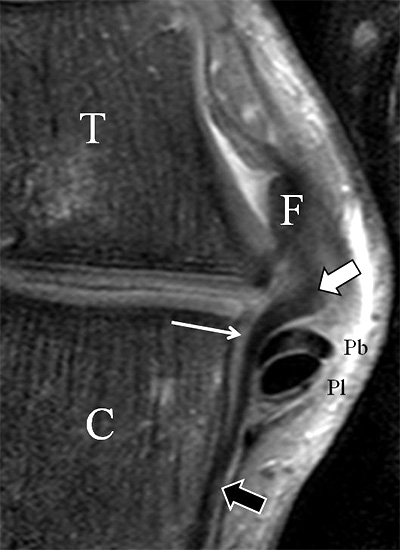

Der Ursprung des Ligamentum fibulocalcaneare liegt unmittelbar kaudal und dorsal des Ursprungs des Ligamentum fibulotalare anterius, so dass gehäuft kombinierte Verletzungen und auch ein gemeinsamer knöcherner Ausriss beobachtet werden. Nach kaudal dorsal verläuft das Band dann nach medial konvex unter die Peroneussehnen. Danach ist ein schräg deszendierender, gestreckter Verlauf bis zum calcanearen Ansatz abgrenzbar (Abb. 10). Dieser zu allen drei Standardebenen schräge Verlauf erschwert häufig die Diagnostik des LFC vor allem bei subtileren Verletzungen. Spezialprojektionen, die dem Bandverlauf orthograd folgen (entweder schräg coronar oder schräg sagittal) erleichtern auch hier die Diagnostik (Abb. 11) insbesondere nicht dislozierter Avulsionen. Assoziierte Verletzungen der Peroneussehnenloge müssen mit beurteilt werden, wobei neben Verletzungen der Sehnen und Sehnenscheiden die Beurteilung des Retinaculum peroneum superius und inferius wichtig ist. In einem Kollektiv von Patienten mit chronischen Außenbandinstabilitäten weisen 50% der Patienten eine Verletzung dieser Strukturen auf 5. Auch hier erleichtern hochauflösende Techniken die Diagnostik (Abb. 12).